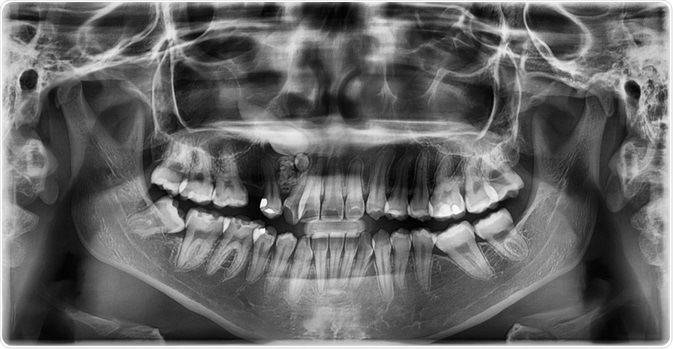

Gardner syndrome is often first identified in a dental clinic, as it is associated with odontomas and impacted teeth at multiple sites that can be both permanent and supernumerary. In fact, about 30% of patients with Gardner’s syndrome have one or more dental anomaly.

Image Credit: Rames Khusakul / Shutterstock.com

Maxillofacial involvement is very common in these patients and can involve skin cysts, pigmentation, and various radiographic anomalies. Odontomas also arise in the paranasal sinuses and mandible, and are rarely painful, generally occurring after puberty.

Multiple osteomas also occur in Gardner's. The most common site for these types of tumors is the mandible, specifically at the angle of the jaw and the inferior surface of this bone. Additional osteomas may be present in the skull, paranasal sinuses, and long bones.

Image Credit: vanzittoo / Shutterstock.com

Osteomas occur early in the course of the disease, typically before colonic polyps become symptomatic or are picked up by radiography. In fact, it is not uncommon for osteomas to develop in Gardner syndrome patients before the condition is even diagnosed. For this reason, the presence of osteomas should arouse curiosity as to the presence of Gardner’s syndrome, as they offer a window of opportunity for early diagnosis and possible prevention of colonic cancer. A number of researchers, therefore, suggest that radiography of the mandible may help to screen for carriers of this condition.

Both osteomas and odontomas may cause the face to become asymmetric. Both sharply-defined radio-opaque lesions as well as fuzzy radio-opaque lesions can be visualized in patients with Gardner's syndrome.